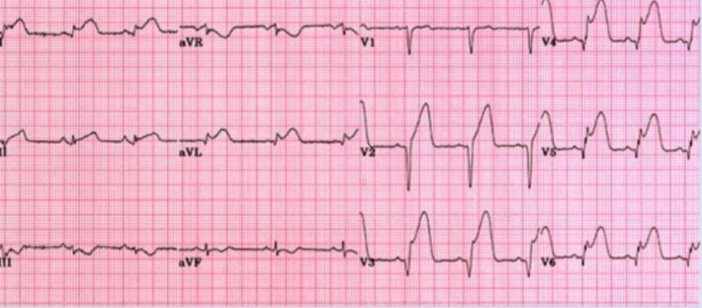

Case 1 Z

What abnormality do you see in this ECG? ST segment elevation in Lead 1, aVL, V2, V3, V4, V5 and V6

What is your clinical diagnosis? Anterolateral ST elevation Myocardial infarction (STEMI)

Mention 2 serum markers will you check to confirm your diagnosis? Troponin T and I, CK-MB

Mention 3 immediate treatment will you give to this patient? Supplemental O2, Morphine, Aspirin

Mention 3 risk factors for this condition? Hyperlipidemia, DM, Obesity, Smoking